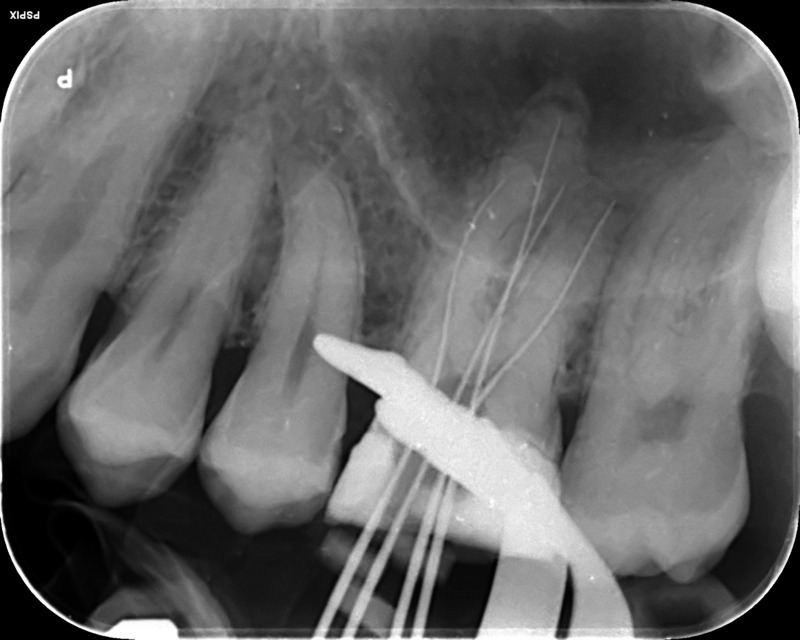

Fractured file removal and re-rct

Pre-op